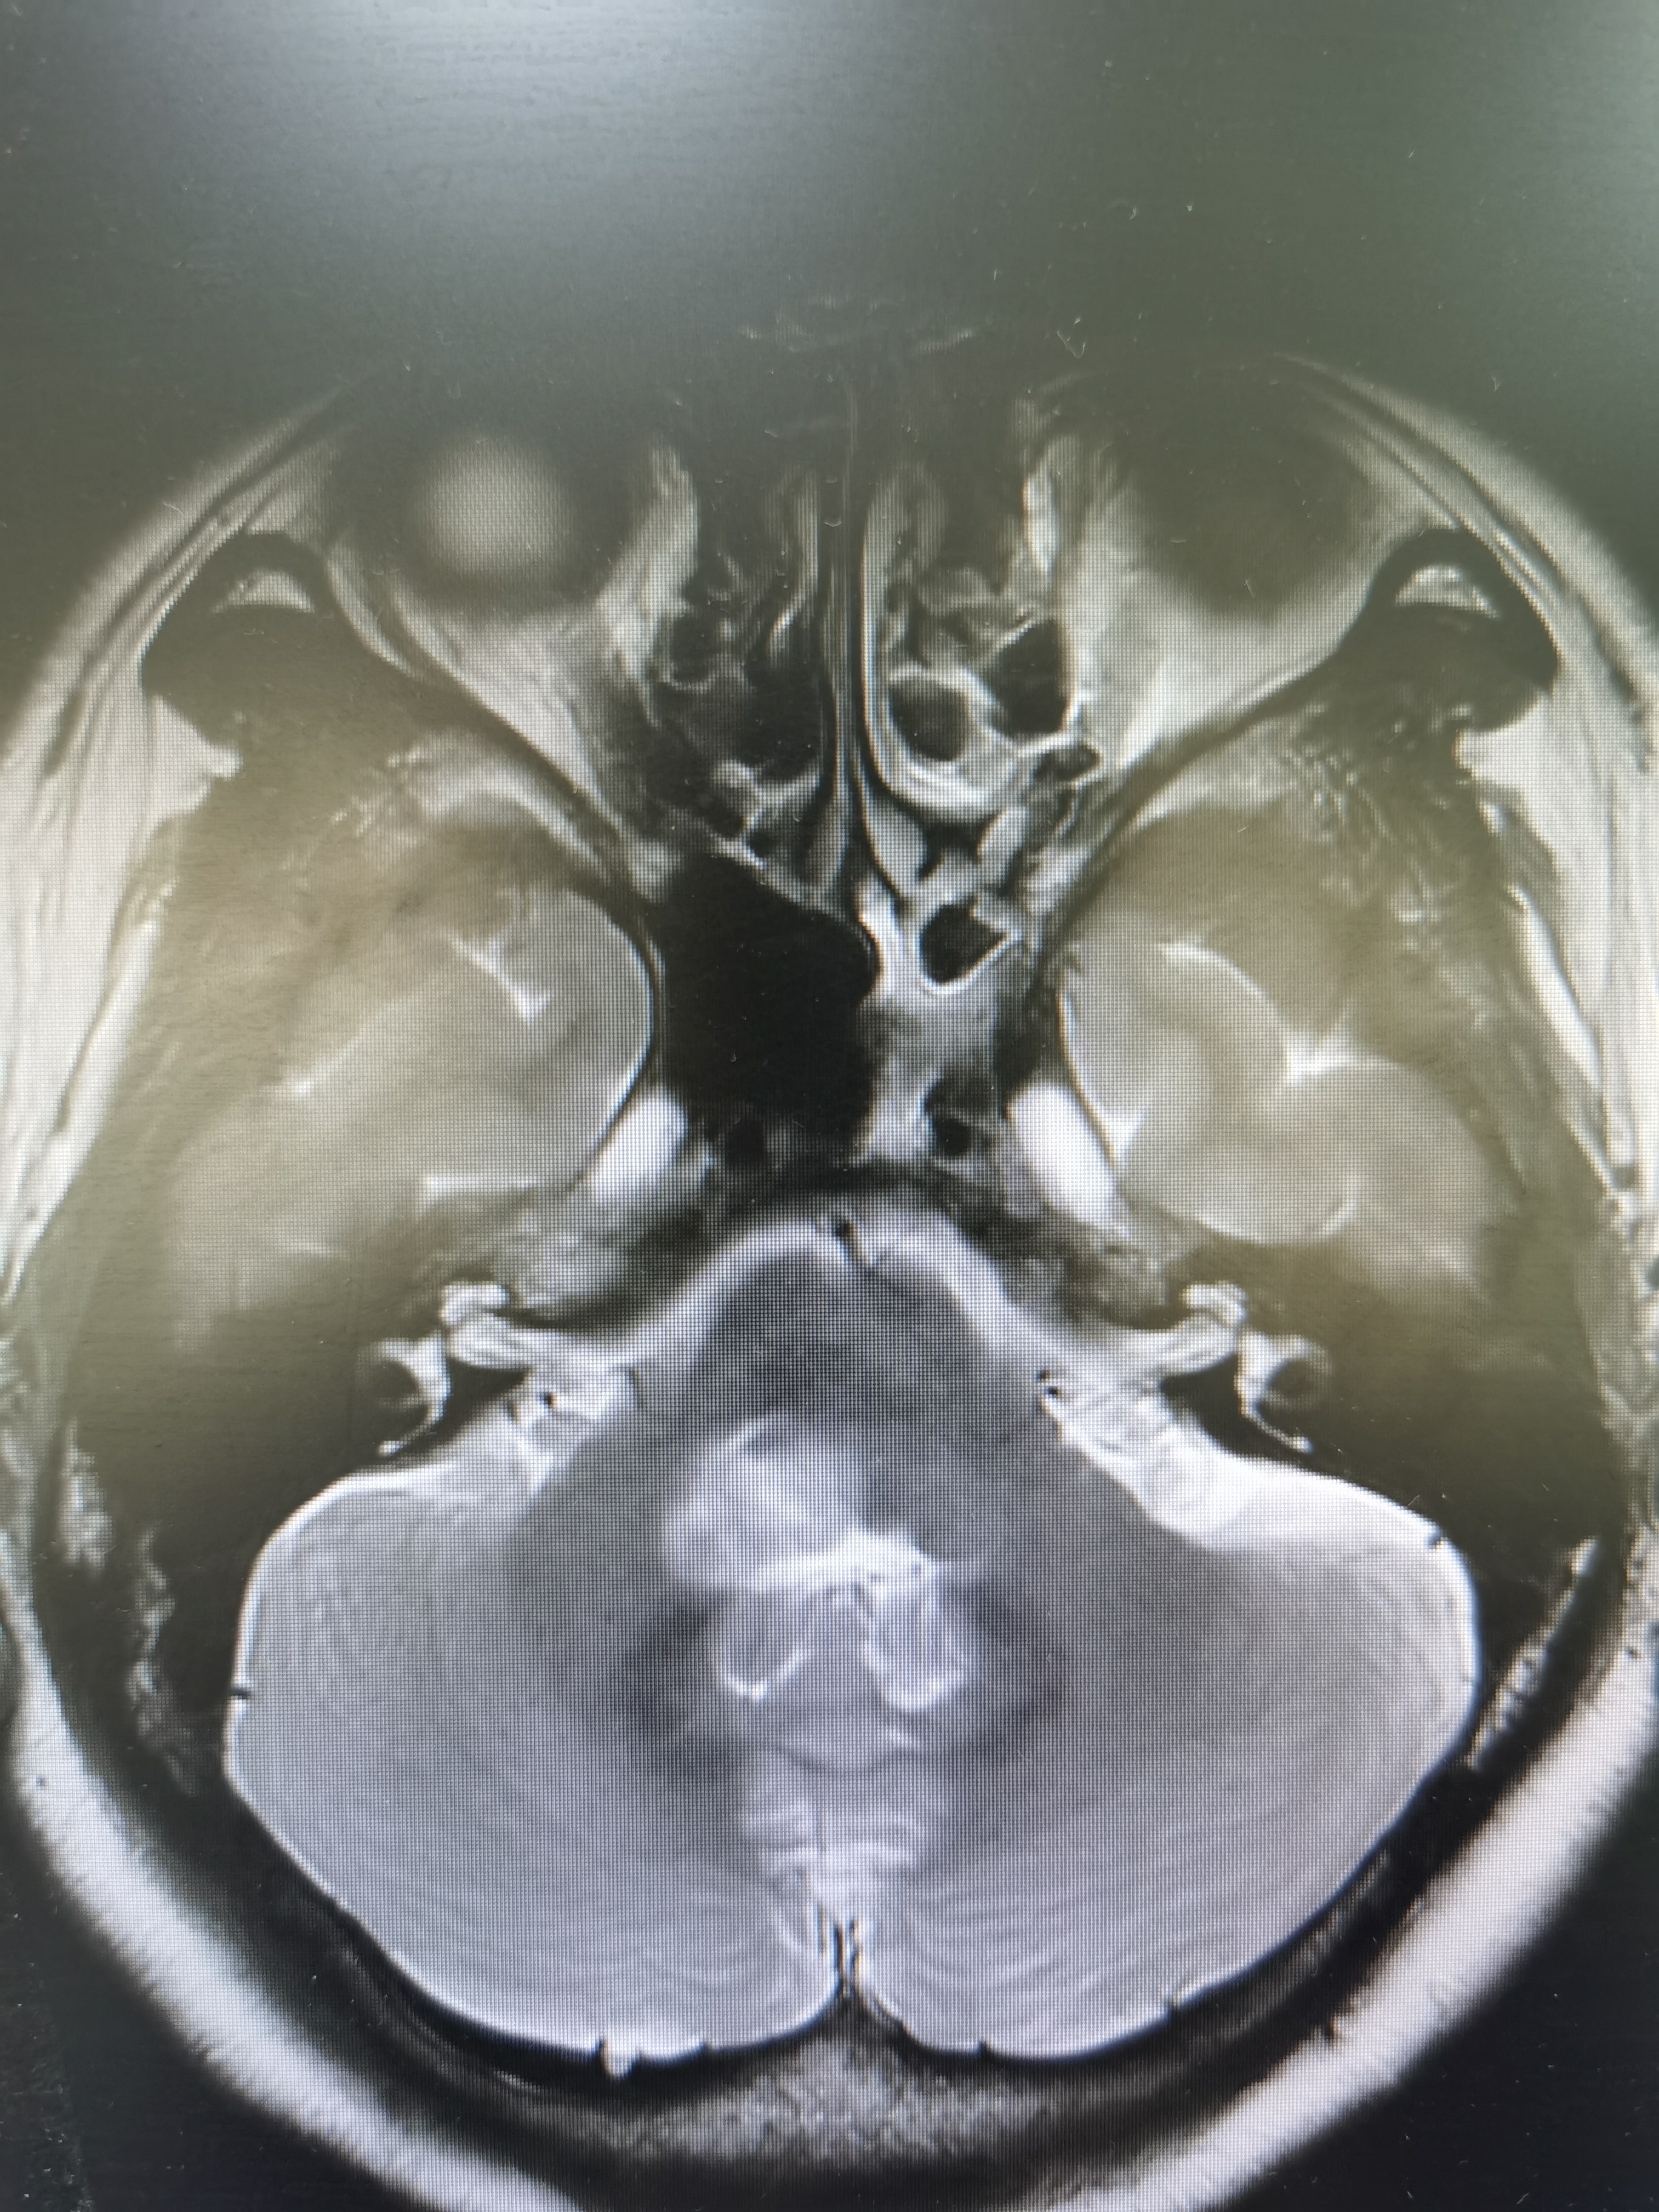

患者女,45岁,因头晕视物模糊伴左侧肢体肌力乏力一月入院。核磁共振报告延髓右侧-桥小脑臂病变,考虑肿瘤可能性大,炎性病变待删。患者及家属强烈要求活检明确病情,科室讨论决定采用立体定向技术活检,因为延髓病变位置过低,Leksell立体定向头架安装及操作有难度,决定采用度若飞新型激光定位技术进行活检。

术前磁共振